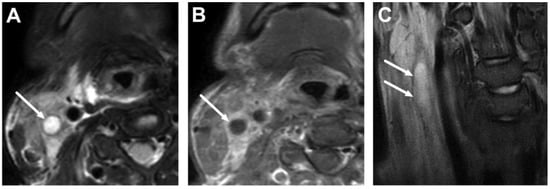

5.1. Lymphadenitis with Purulence vs. Necrosis

5.2. Cystic Masses